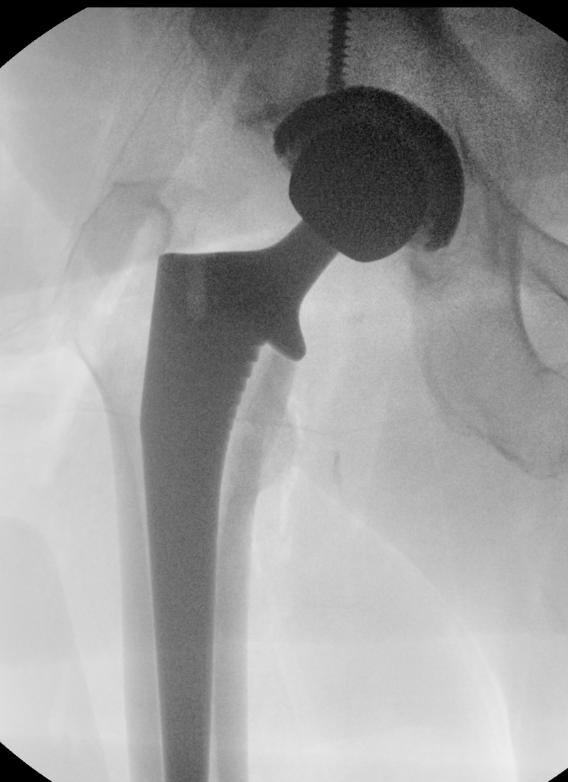

Fluoroscopy

Sun et al Arch Orthop Trauma Surg 2024

- meta-analysis of use of intra-operative fluoroscopy versus conventional navigation in THA

- fluoroscopy reduces incidence of LLD